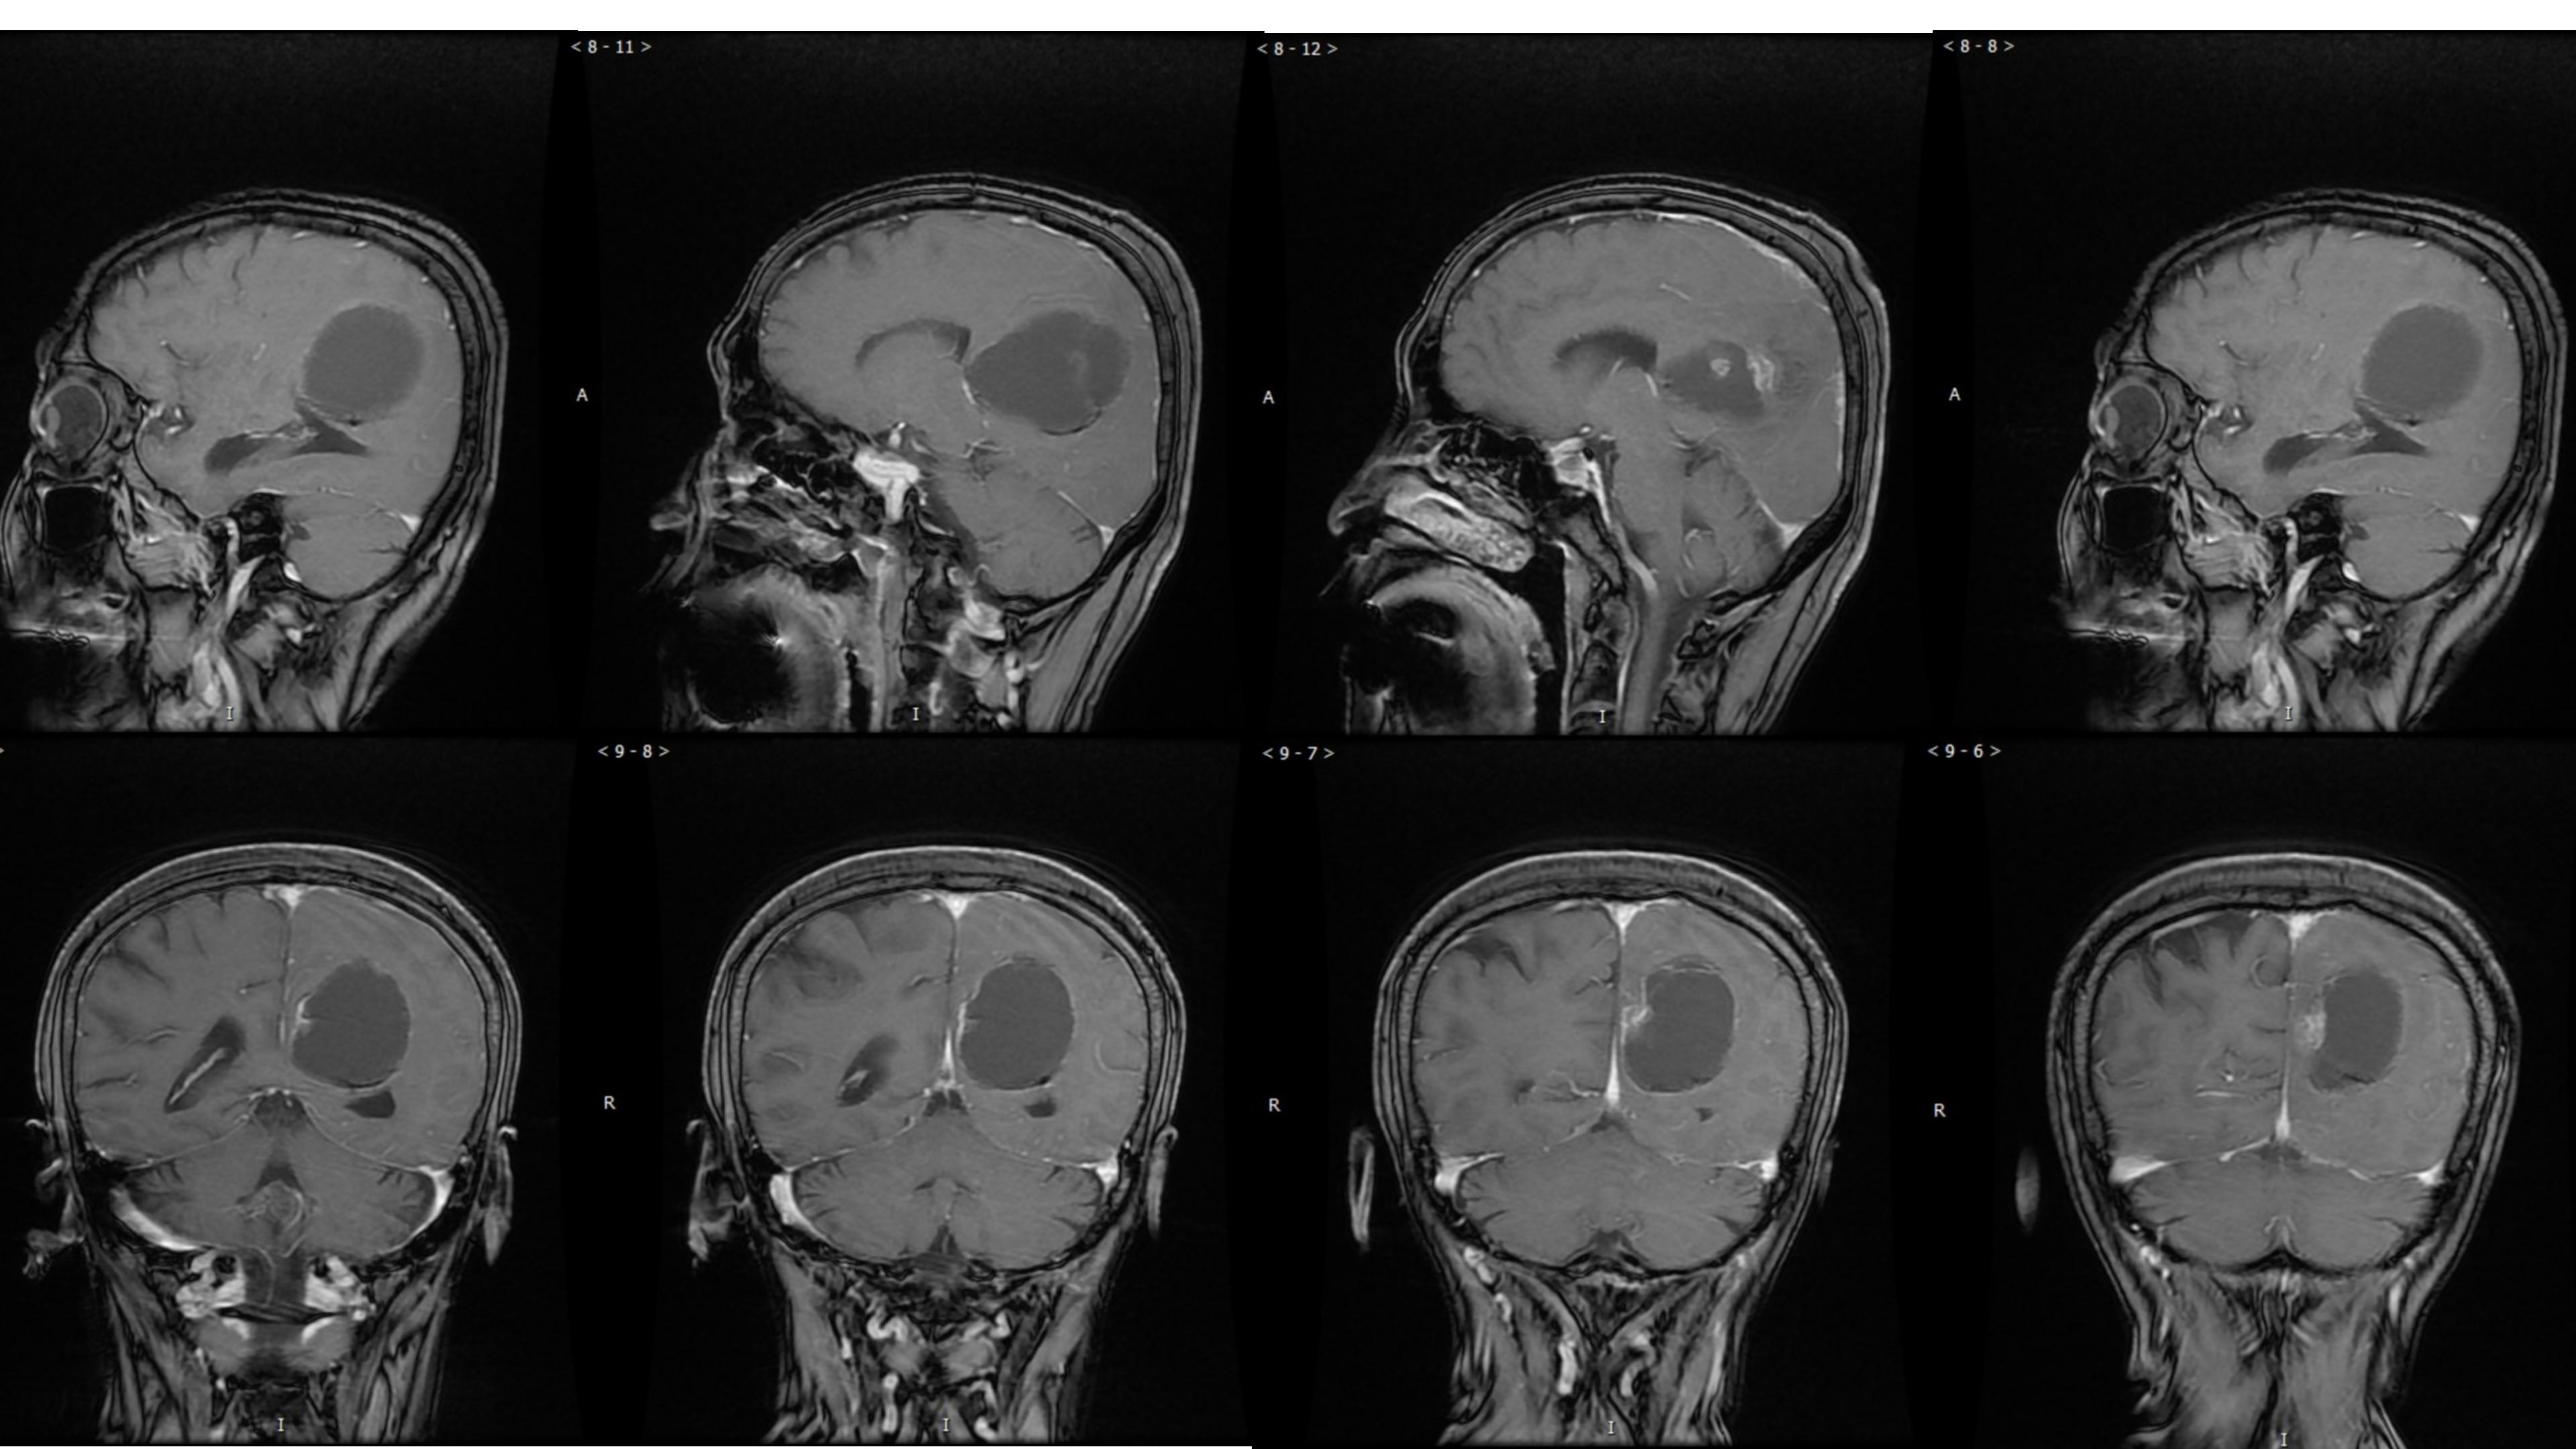

幕上毛细胞型星形细胞瘤(WHO Ⅰ级)